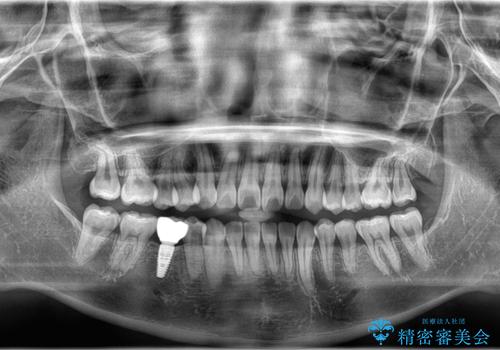

下顎前歯の叢生が整い、右下5番部には機能的かつ審美的なインプラント補綴が完了しました。

咬合全体のバランスも改善し、長期的な安定性が期待される状態となりました。

患者様にも「長年気になっていた前歯のがたつきも一緒に治せてよかった」と喜んでいただけました。